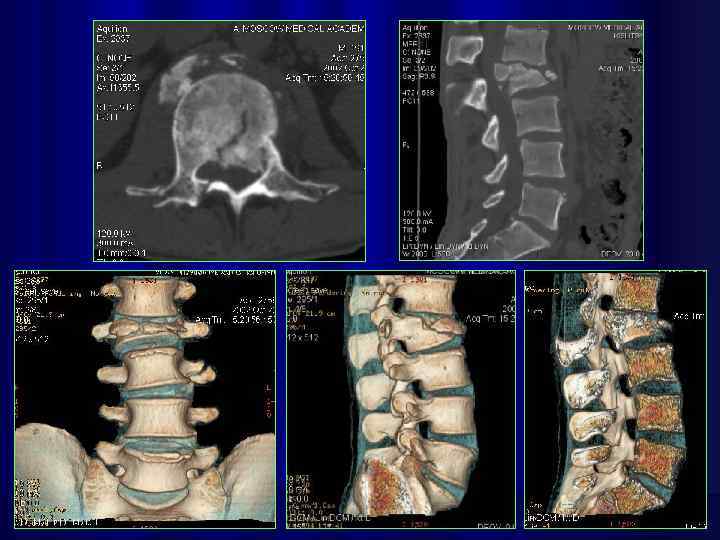

Дегенеретивно-дистрофическое поражение позвоночника

3 -d реконструкция изображений на 64 срезовом спиральном КТ